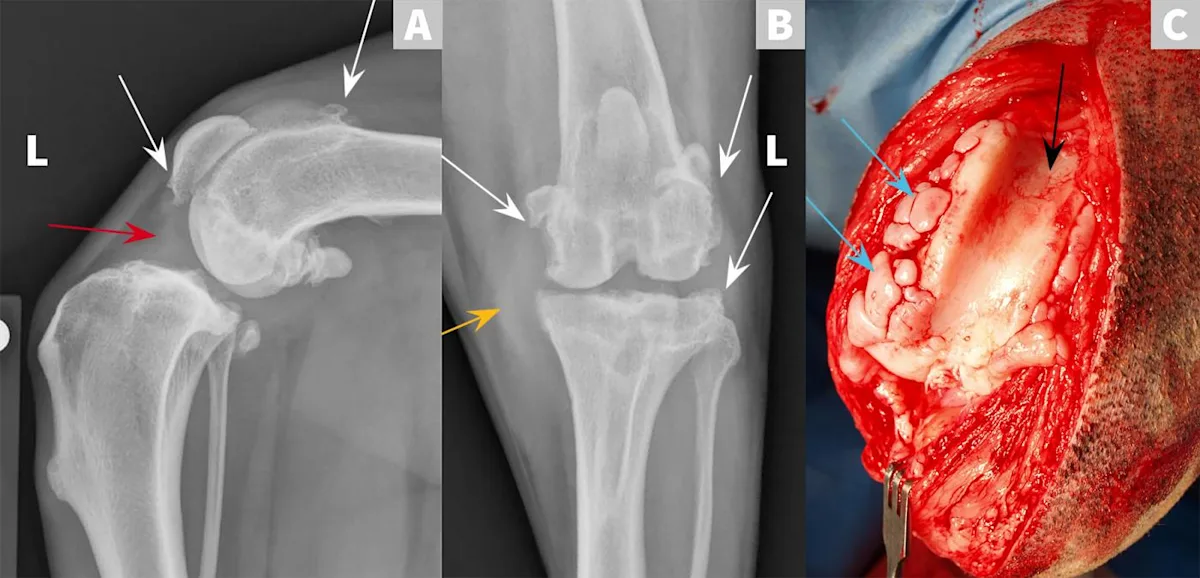

FIGURE 1

Cranial cruciate ligament (CrCL) disease, a common cause of hindlimb lameness in dogs,1,2 is a chronic degenerative process that results in stifle instability, articular cartilage wear, and, in some cases, meniscal injury. Surgery is often recommended for rapid stifle joint stabilization, treatment of meniscal injury, and to achieve earlier return to clinical function.2,3  Figures A and B show lateral and craniocaudal radiographic projections of a left stifle with CrCL rupture. They demonstrate periarticular new bone formation (osteophytes) on the tibial plateau, patella, fabellae, and trochlear ridges of the femoral condyles (white arrows). In Figure A, there is an increase in soft tissue opacity within the joint space, causing cranial displacement of the infrapatellar fat pad, which is most consistent with joint effusion (red arrow). In Figure B, there is an increase in soft tissue opacity on the medial aspect of the joint that is consistent with thickening of the medial portion of the joint capsule (ie, “medial buttress”, yellow arrow). Figure C shows an intraoperative view of a left stifle joint with CrCL rupture following a craniomedial arthrotomy and lateral luxation of the patella. Osteophytes are present on the trochlear ridges (blue arrows) and cartilage degeneration is visible in the trochlear groove (black arrow).